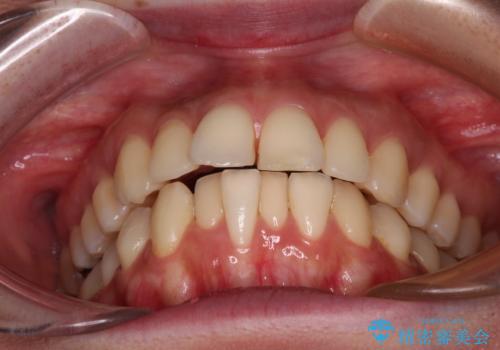

- 口元の閉じにくさを気にして来院された患者様です。

上下ともに歯列が前方に突出していたため、上下左右の第一小臼歯4本を抜去し、ワイヤー装置による矯正治療を行うこととしました。

舌の突出癖による影響もあったため、舌のトレーニングを並行して実施しました。